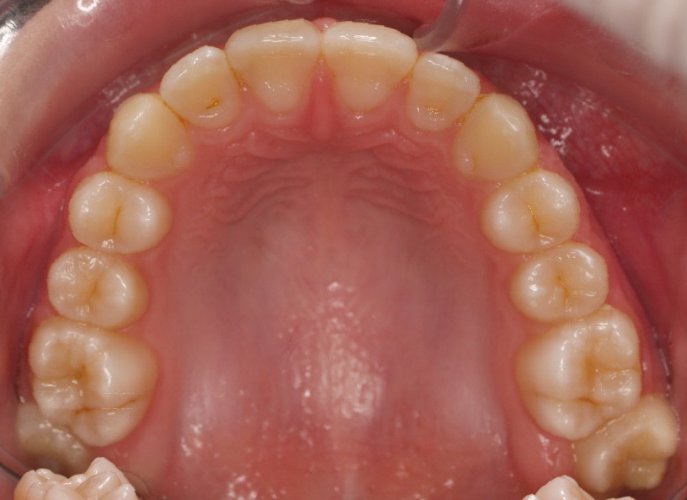

El paciente A.J. de 11 años, acude a nuestra consulta con apiñamiento maxilar importante. El canino lateral (12) está en mordida cruzada. Presenta una Clase II molar y canina, y la línea media está desviada. Se realizó un tratamiento con brackets autoligables metálicos de smartclip 022. La duración del tratamiento fue de 22 meses.

El paciente actualmente ha terminado el tratamiento con brackets y lleva una contención fija de 2-2 en maxilar y 3-3 en mandibular; para complementar también lleva una férula ESSIX durante la noche.